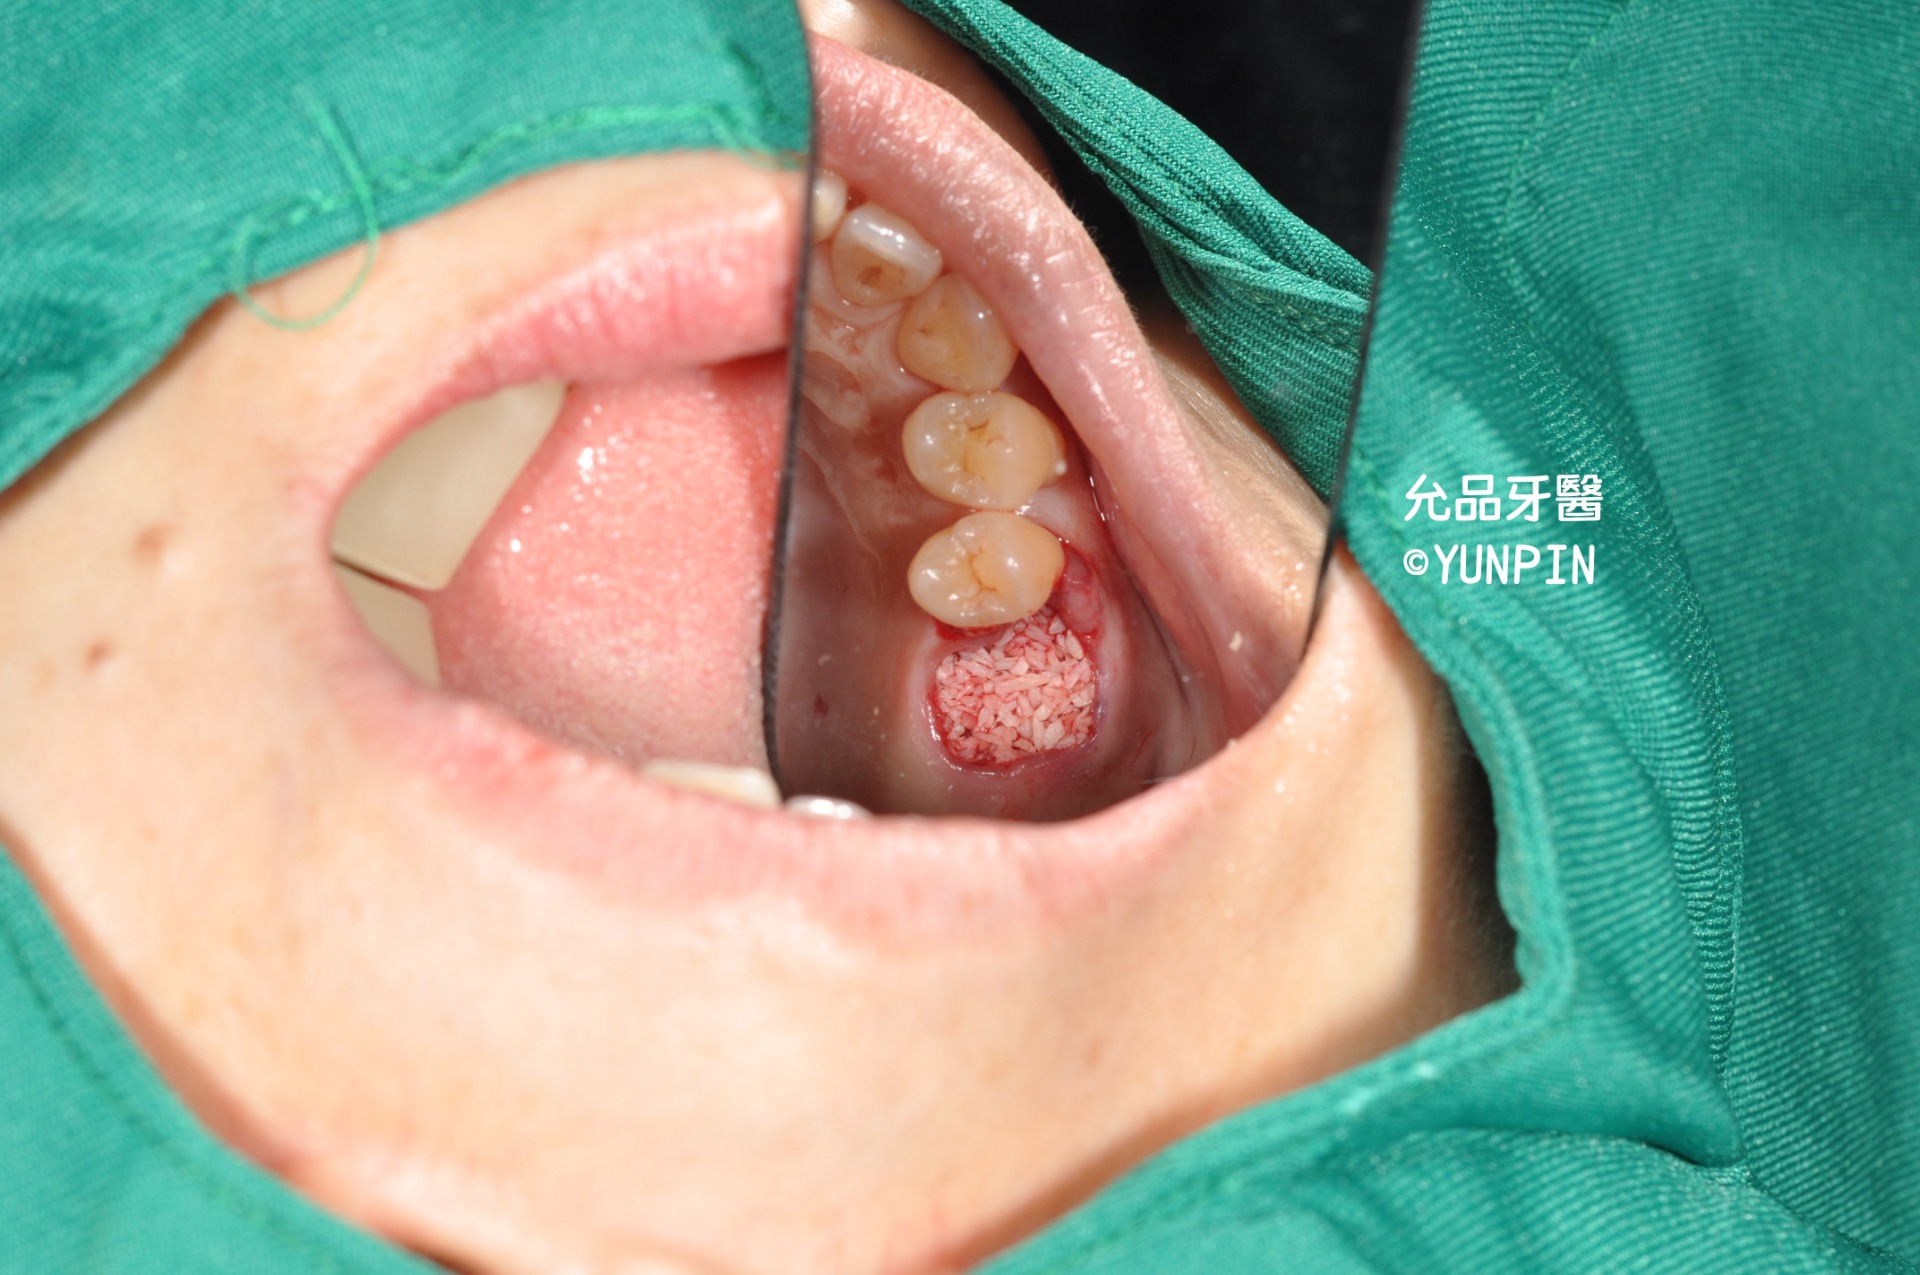

拔除後牙窩

牙窩進行骨粉填充